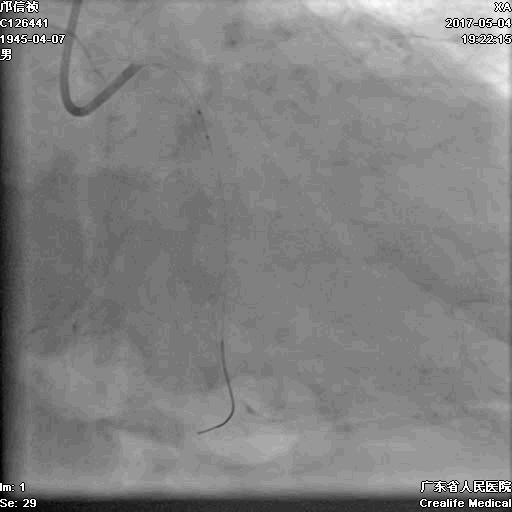

第二步:处理LCX

Fielder XT-A,Gaia First ---在微导管支撑下通过闭塞病变

LCX植入支架

2.0*10mm球囊

2.75*22mm药物支架